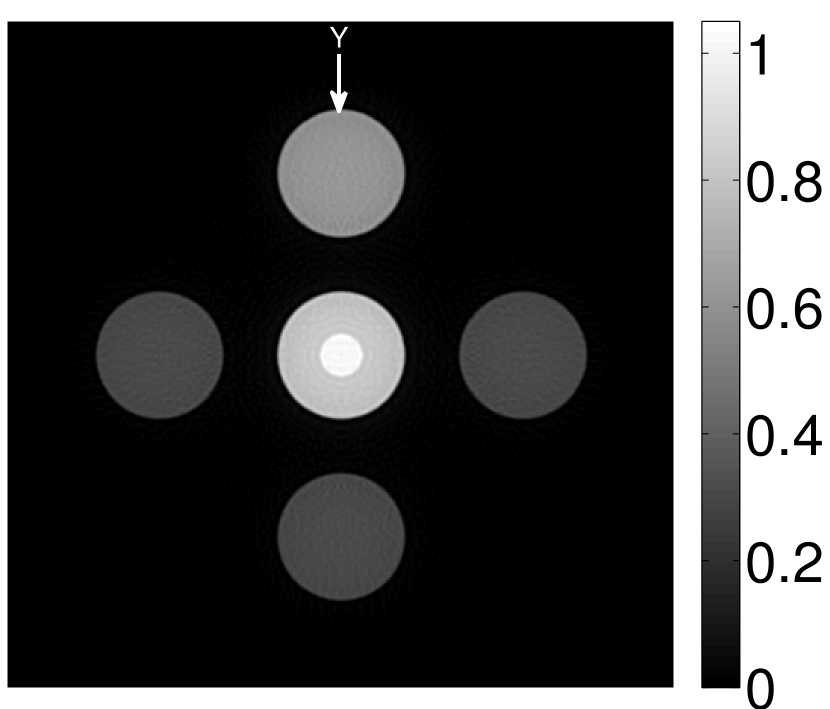

The images and EIRs reconstructed by use of the VP algorithm that was based on the 2D imaging model that neglected the SIR are shown in Figures 15 and 16. The latter figure contains results corresponding to different values for the regularization parameter . From Fig. 15, it can be observed that use of the conventional iterative method that utilized the measured EIR resulted in distortions and loss of details in the reconstructed images. Use of the VP algorithm improved the contrast and the details in the reconstructed images (Fig. 15(c) and 16(a)). Furthermore, the images reconstructed by use of the VP algorithm had a more uniform background.

In Figure 17, the results corresponding to use of the 3D imaging model that incorporated SIR effects are shown. The EIR estimated by the VP algorithm is also shown. In Figure 18, images and EIRs reconstructed by use of the VP algorithm with different regularization parameters values are shown.

Similar to the case described above where the transducer SIR was neglected, these results reveal that use of the VP algorithm can produce images with a cleaner background and enhanced spatial resolution than yielded by use of a conventional iterative algorithm that employed the measured EIR. For example, detailed information regarding the vessels near the organ’s periphery was better preserved by the VP algorithm than by the conventional iterative algorithm. These images corroborate our assertion that the VP algorithm can significantly reduce the artifacts and distortions in the reconstructed image. It is also worth pointing out that, unlike the numerical phantom studies, the artifacts and distortions in the images may be caused not only by the inaccurate EIR but also by other factors, such as neglecting acoustic heterogeneities and the variation of the EIRs among the elements of the transducer array. In such cases, the EIR estimated by the VP algorithm represents an effective system impulse response that minimizes the inconsistency between the measured data and the imaging model.